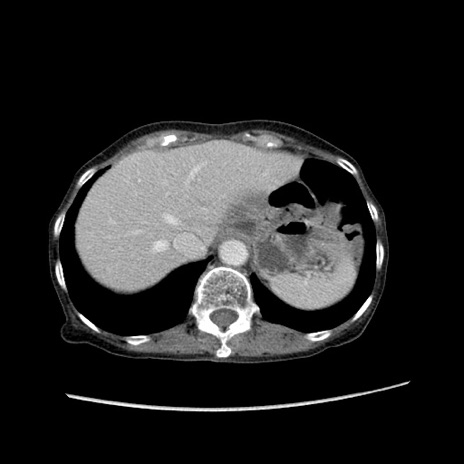

症例25(横断像)

【症例】80歳代女性

【主訴】胸のつかえ感

【現病歴】約9時間前に食後から胸のつかえた感じあり、嘔吐あり、来院。

【既往歴】胃癌(全摘)、胆摘、虫垂炎

【身体所見】心窩部に圧痛あり、反跳痛なし。

【データ】WBC 5700、CRP 0.05